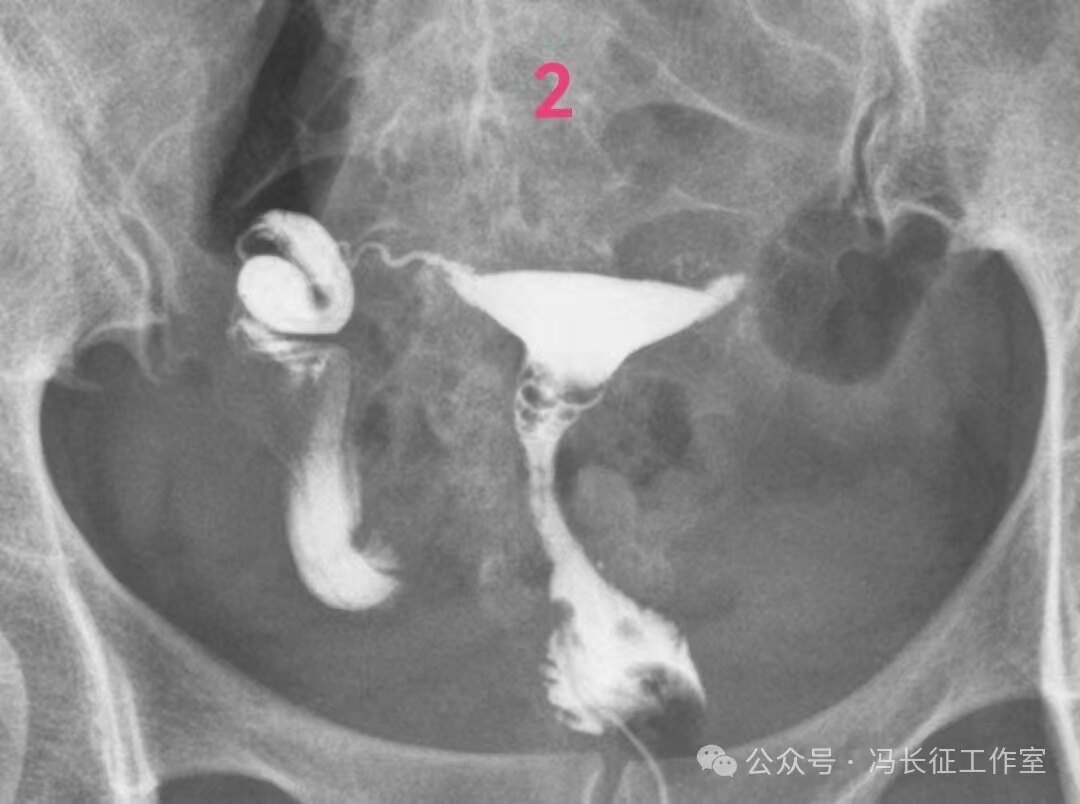

下面是一例输卵管功能良好的双侧输卵管积水的图片

双侧输卵管输卵管走行较自然柔软,近端和宫腔相通,输卵管粘膜丰富、单囊,双侧输卵管都向中间的子宫聚拢(提示输卵管系膜好),这些都提示双侧输卵管功能良好。虽然伞端没有造影剂进入盆腔弥散,输卵管管壁厚度和周围粘连情况未知;但是,从前面的信息可以初步估计输卵管功能良好。所以就给她做了腹腔镜行积水远端造口手,恢复伞部的拾卵功能,术后自然怀孕生育。